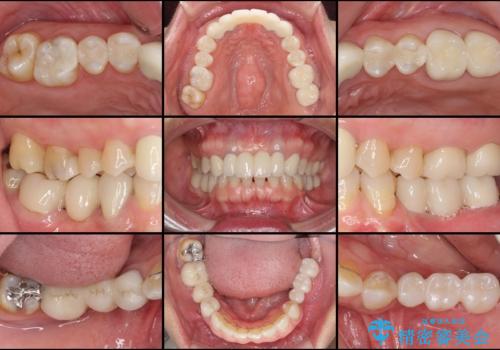

遠方からの来院であったので、1回の治療時間を長めにし、できる限りの処置を集中して行うことで、来院回数を減らすことができました。

矯正治療までは考えていなかったそうですが、物が挟まっていた前歯のスペースがなくなり、矯正治療を行って良かったとのことでした。

初診カウンセリングを含めて13回の通院で治療を終えることができ、患者様には大変満足していただきました。